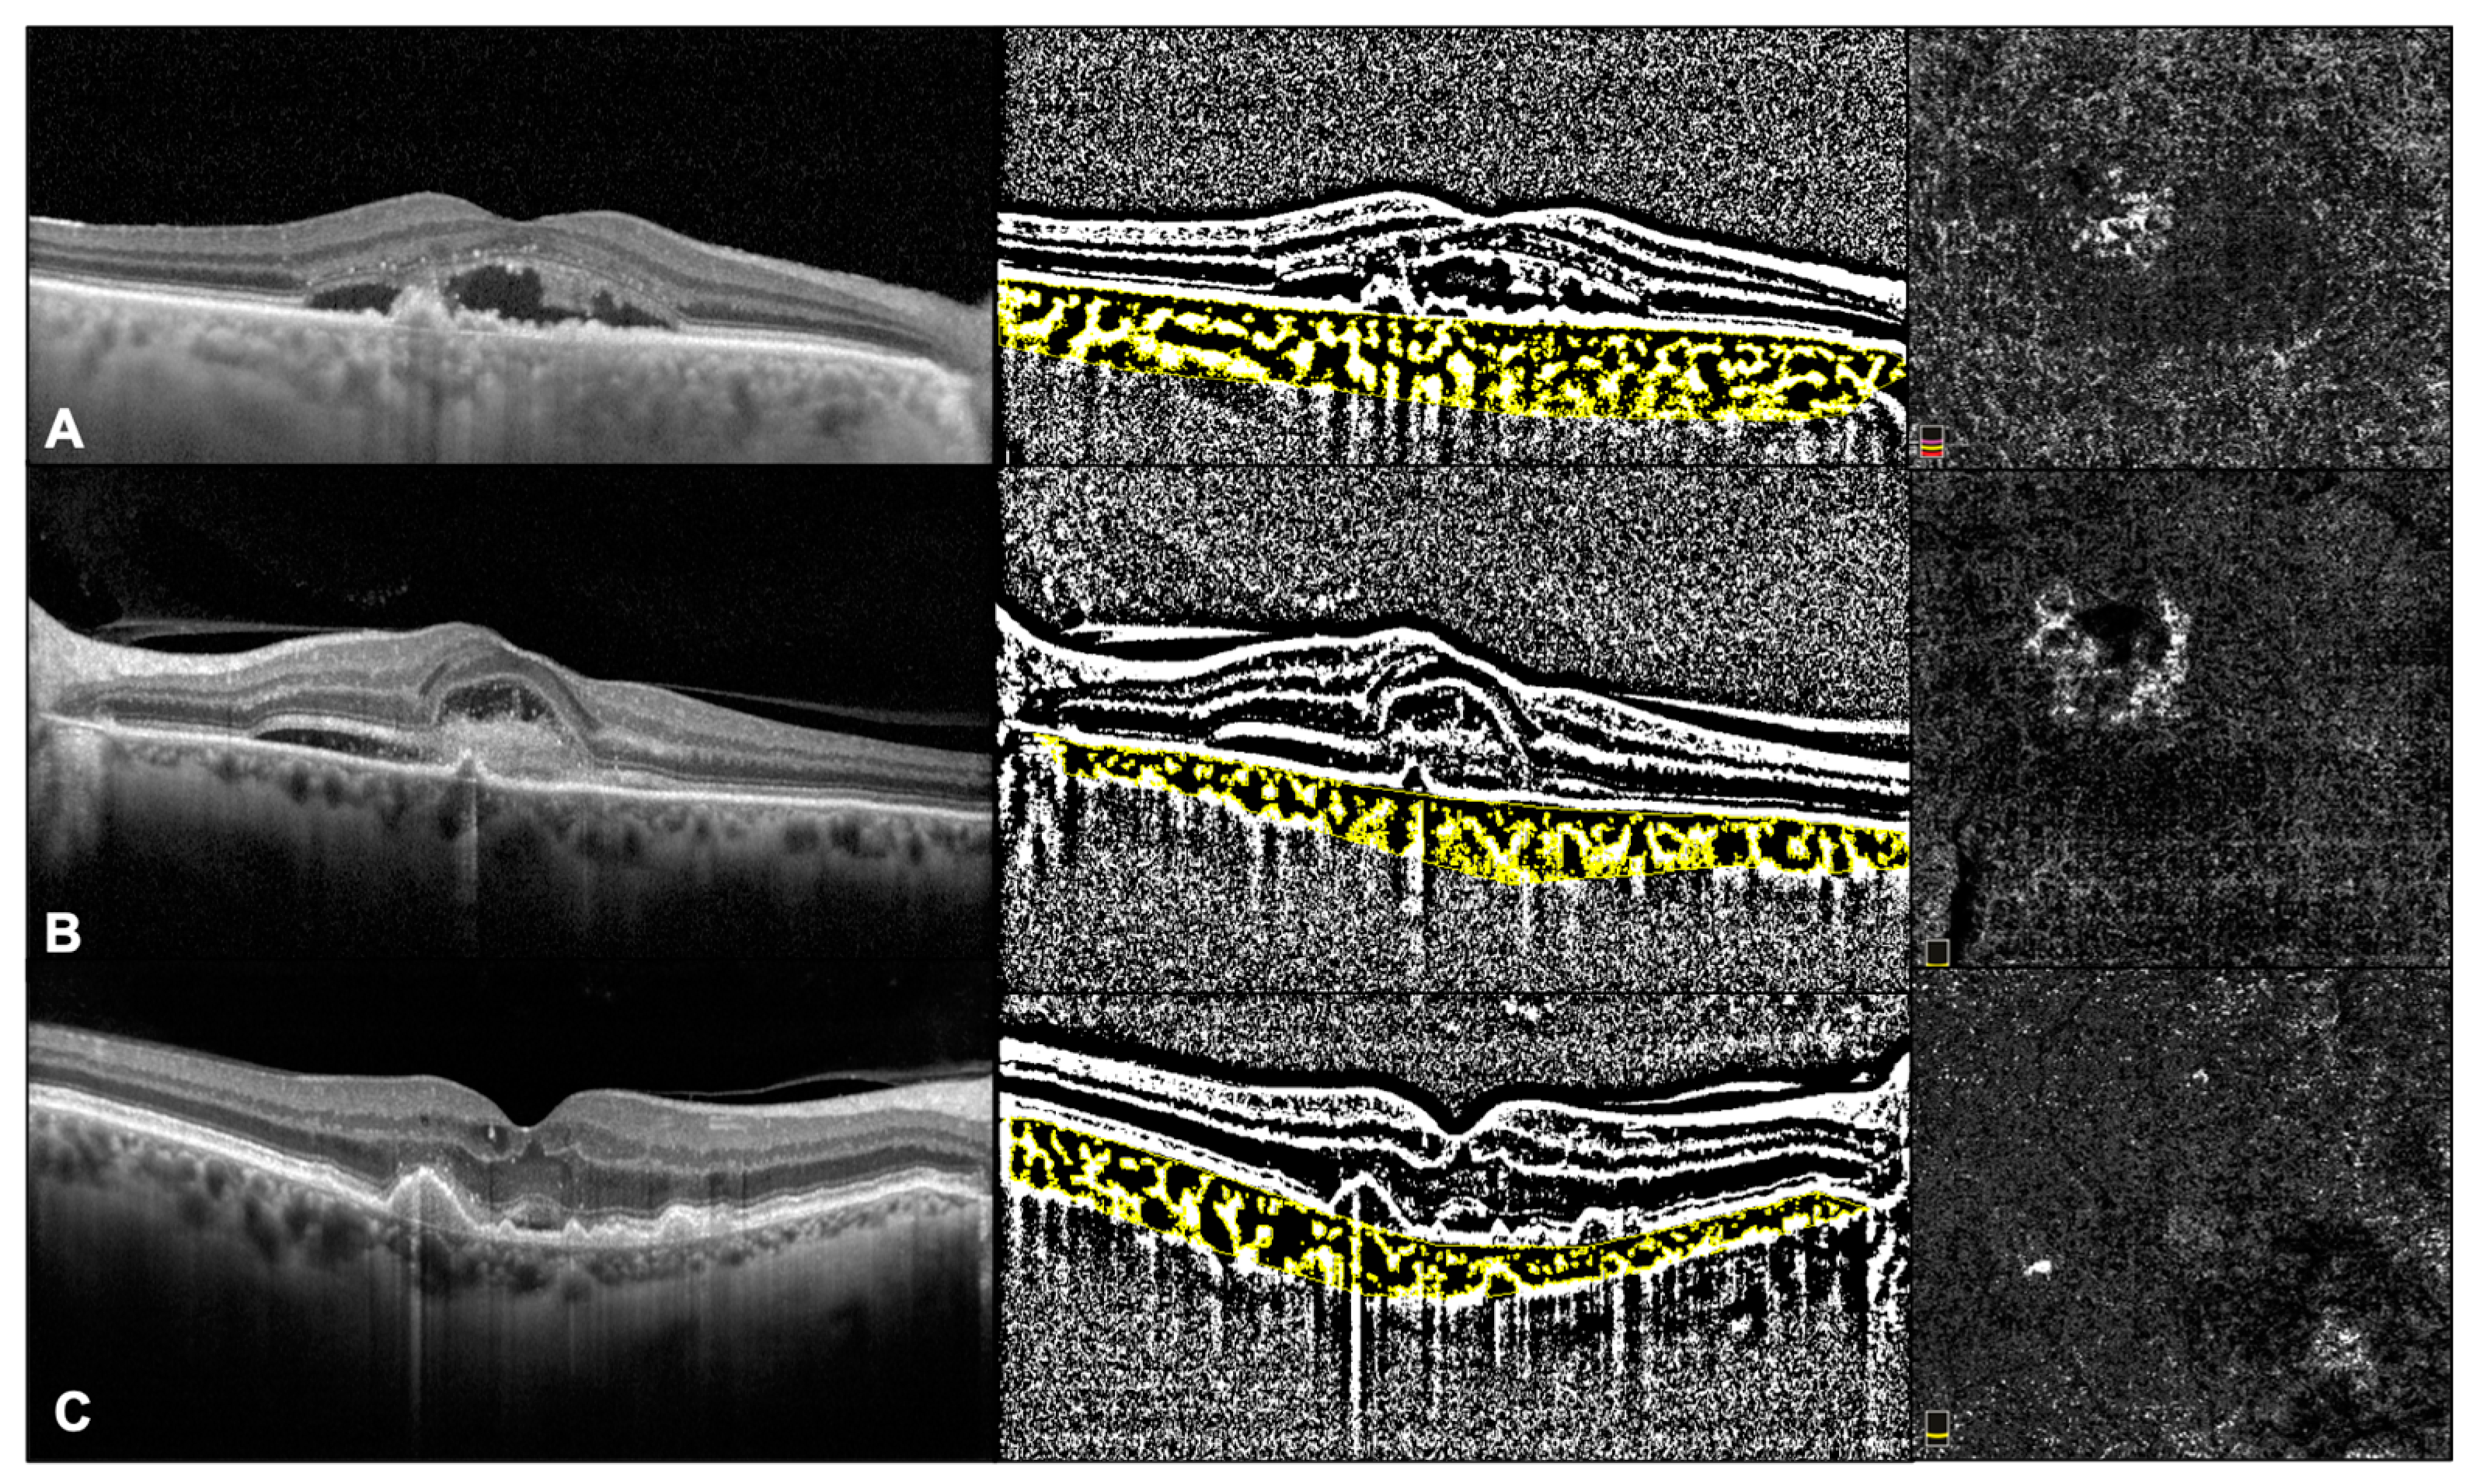

2.2. Imaging Protocol

2.3. OCT Analysis

2.4. OCTA Analysis

3.2. SD-OCT and OCTA Parameters